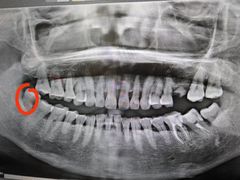

• 爱尚大众口腔(南湖花园门诊)

• -爱尚大众口腔(南湖花园门诊)